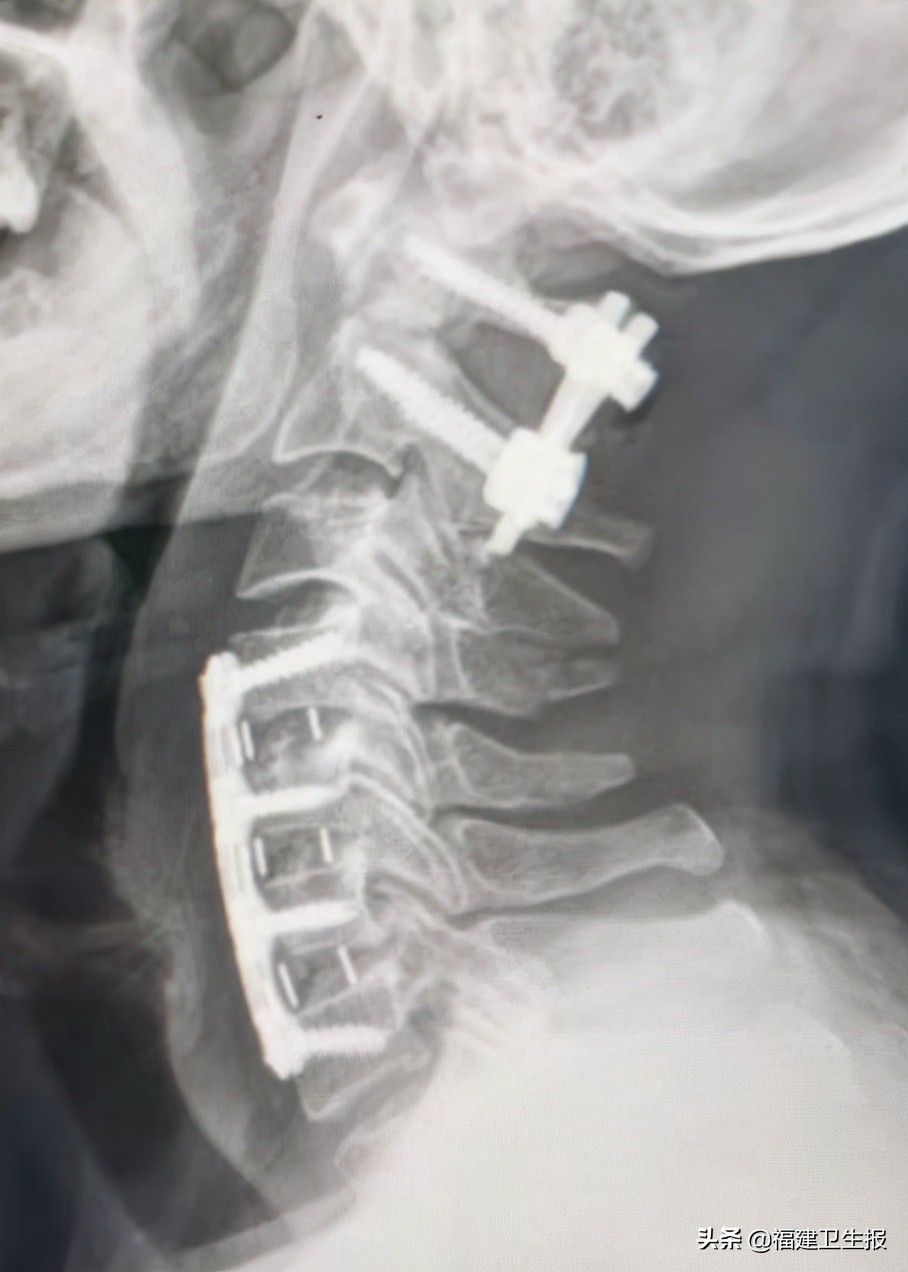

术后患者很快恢复清醒,四肢开始活动。术后第一天患者双上肢可自行举起,双手握力开始恢复。术后第5天患者各引流管均拔除,佩戴颈托自行下地步行良好,双上肢肌力恢复正常,下肢肌力正常,各项生活可自理,复查颈椎X线片及颈椎CT见枢椎齿状突骨折及寰椎复位良好,内固定精准在位。

▲术后复查颈椎X光

▲CT